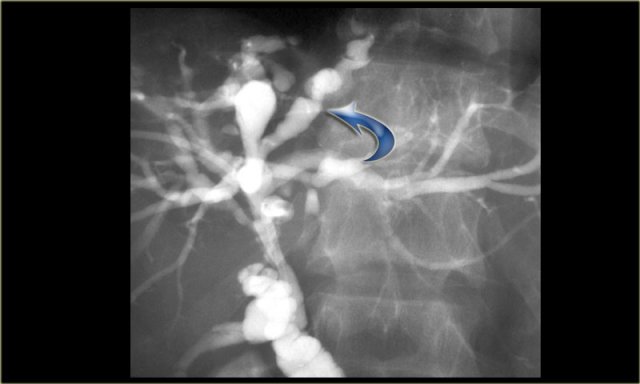

On the left we see images of a patient with Caroli disease.

Notice the intrahepatic duct dilatation and the normal caliber of the choledochal duct (extrahepatic bile duct).

The hallmark of Caroli disease is intrahepatic duct dilatation.

The dilatation can be very large and saccular as seen in the case on the left or it can be very linear.